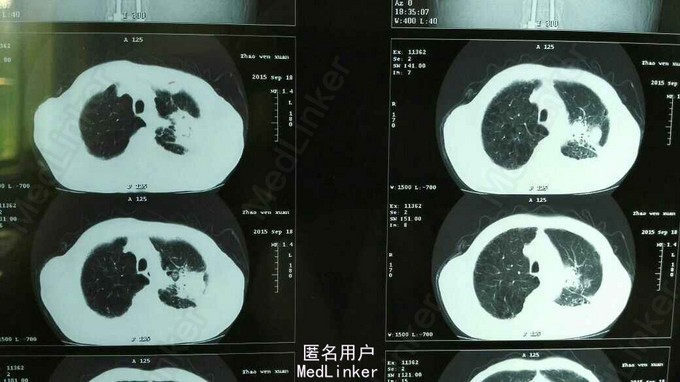

TPR:38.0 80 20,血压130/80mmHg。左肺下叶叩诊呈浊音,听诊呼吸音低,双肺可闻及少许湿胸罗音,未闻及喘鸣音。心脏及腹部查体未见明显异常。 辅助检查见图。

继发性肺结核 左侧 涂阳 初治 尿毒症 原发性高血压3级 极高危 治疗方案:2HRZE/4HR